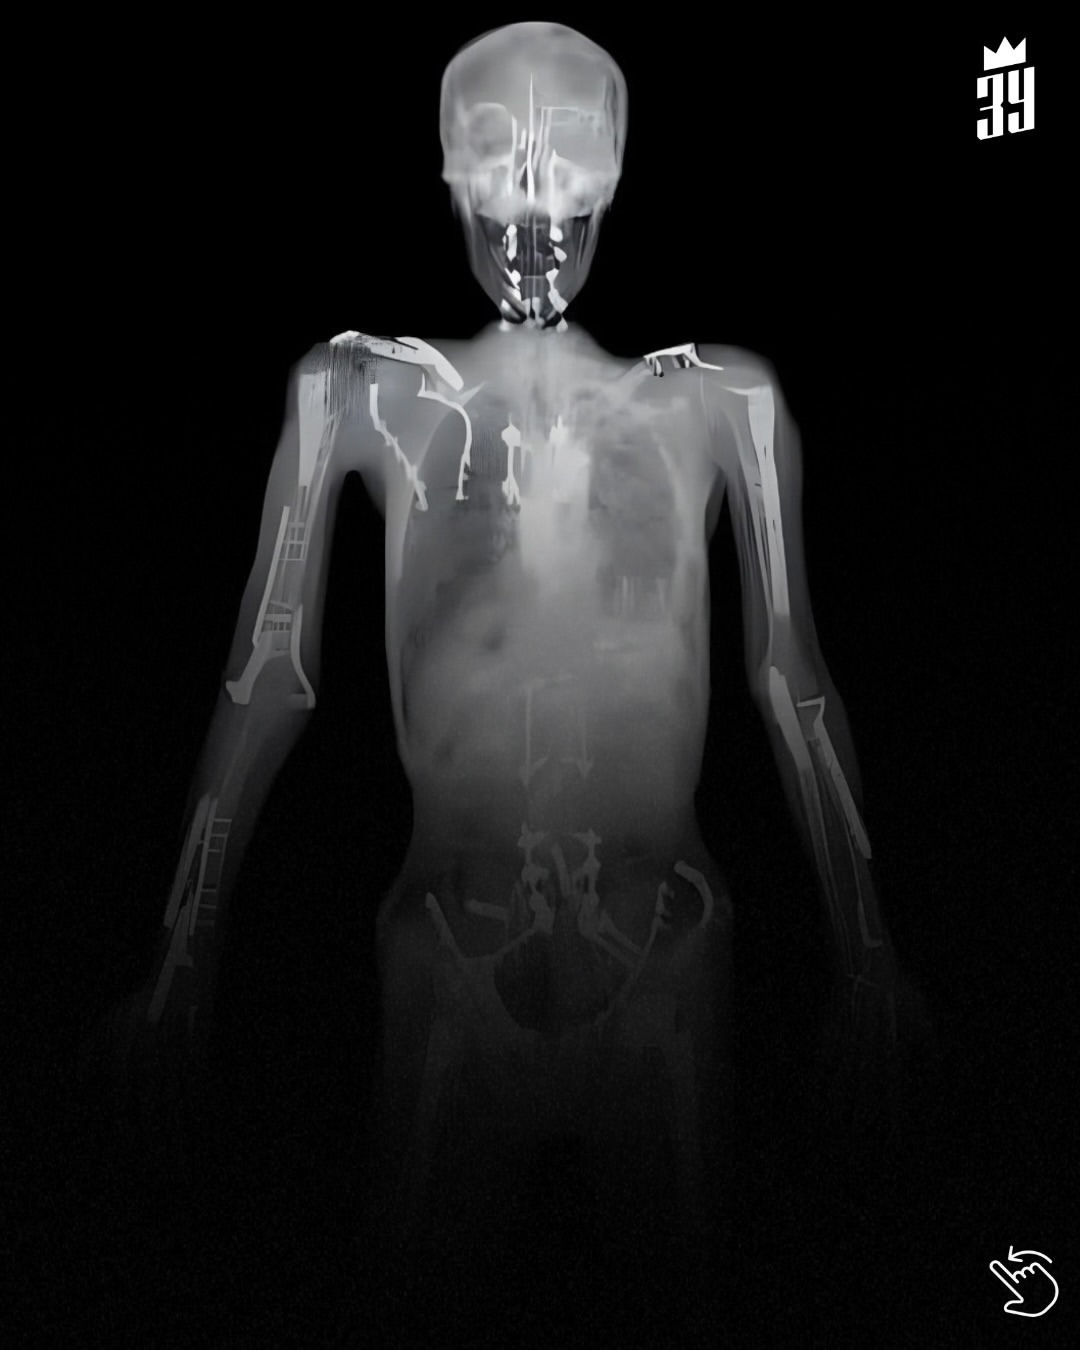

Легенда мотоспорта Трэвис Пастрана более двух десятилетий переопределяет пределы возможного, и его медицинские снимки показывают истинную цену этой амбиции. Рентген выявляет пластины для сращения плеч и позвоночника, стержни и винты, которые остались после почти смертельных аварий, начиная с аварии в грузовике на Daytona 500 в 2003 году и переворота на ралли в 2006 году, в результате которого его бедренная кость была сломана в 28 местах. Позже Пастрана прошёл сращение шейного и поясничного отделов позвоночника, и титановые импланты стали постоянной частью его организма.

Но это не просто история о травмах — это свидетельство стойкости. Под этими имплантами скрывается философия риска и постоянного совершенствования: гонки — это не только скорость, но и адаптация. Пастрана продолжил свои подвиги: сделал двойное сальто на X Games, выиграл раллийные чемпионаты и выступал в NASCAR и IndyCar — его восстановленное тело стало ещё одной частью его гоночного шасси.